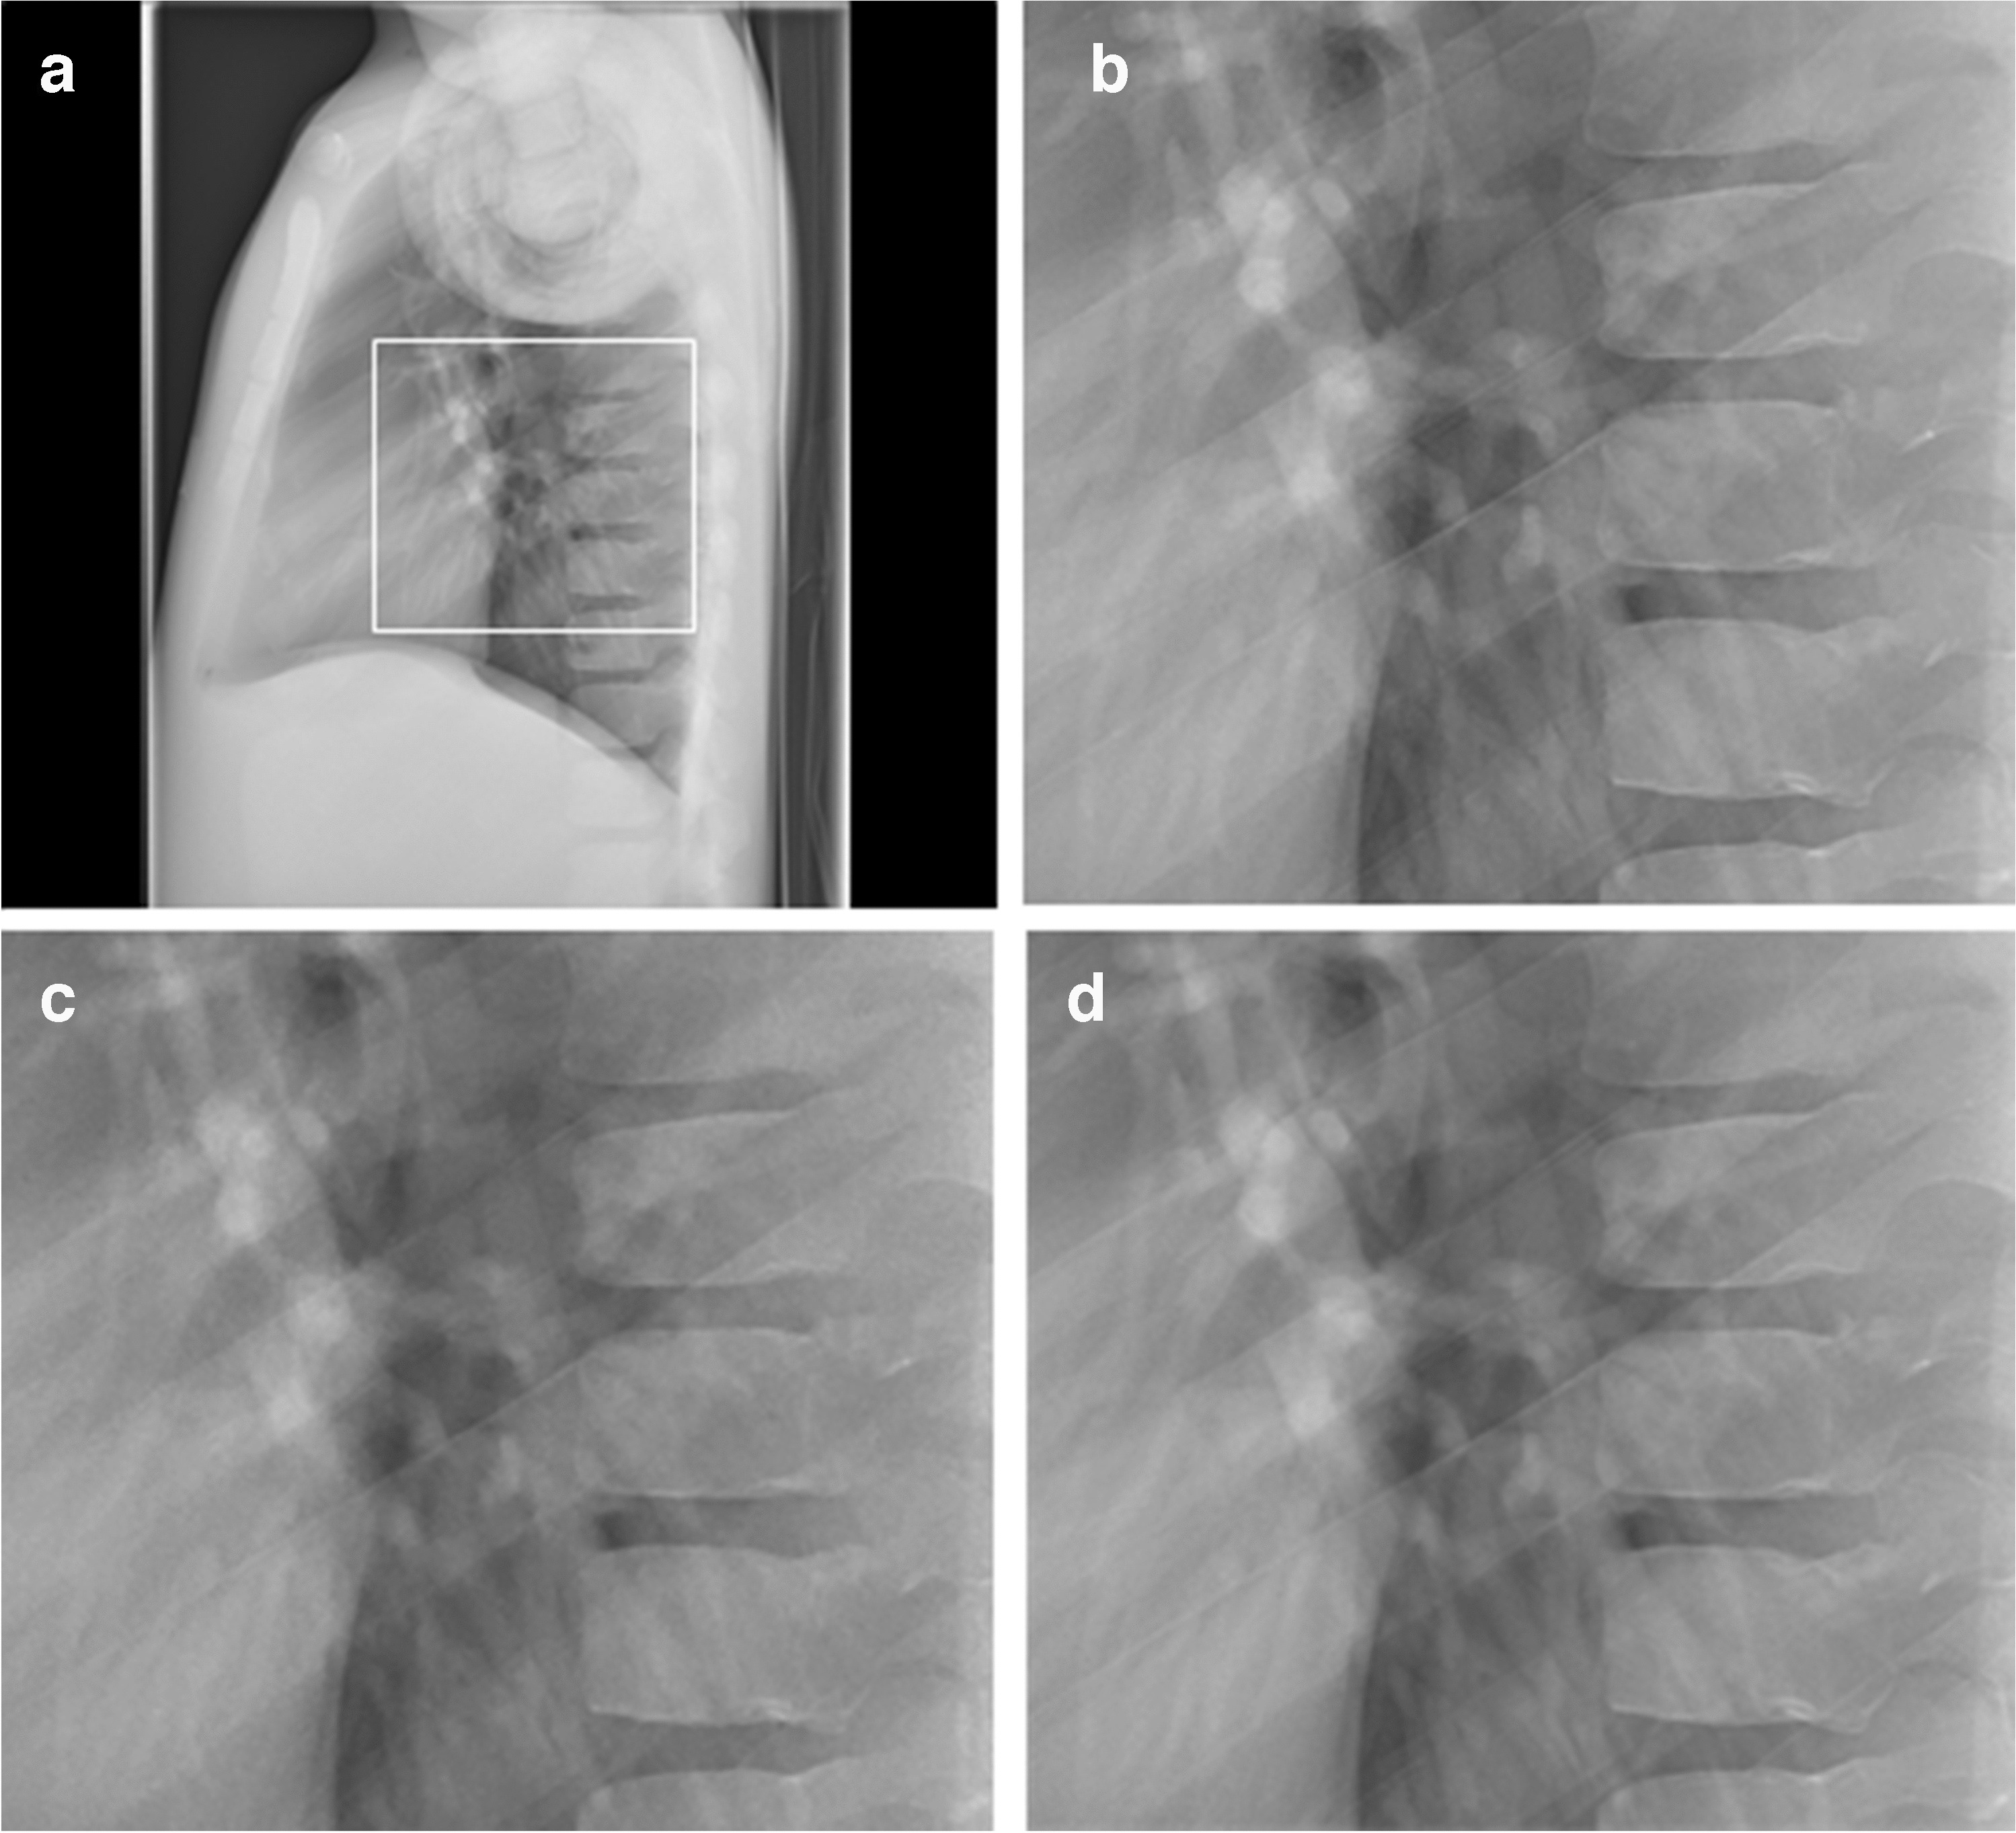

Anteroposterior and lateral images of both phantoms were acquired with the routinely applied digital postprocessing (standard noise reduction) as well as with INR; see examples in Figs. 1 and 2. INR can be applied at a level of 1–10, ranging from the lowest (1) to the highest (10) influence of INR on noise reduction. In this study, a medium level of 5 was used for all images.

Fig. 2

Lateral chest radiographs of the PBU-70 phantom (Kyoto Kagaku). a Dose level 100% with standard noise reduction. The image shows the magnified region in images (b-d) (box). b-d Magnified images at dose level 100% with standard noise reduction (b), dose level 25% with standard noise reduction (c), and dose level 25% with intelligent noise reduction (d)